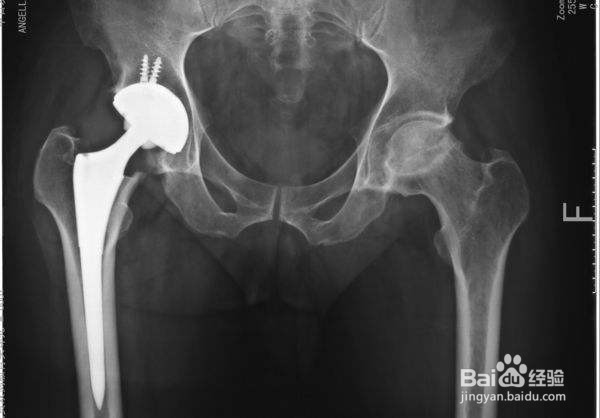

3、误区三,股骨头坏死只能进行置换。

股骨头坏死的治疗防止有许多种,进行股骨头置换有很大的手术风险及后续问题,要慎重考虑。除了股骨头置换还有一些其他的治疗方式,比如中医的饱受治疗可根据患者自身需要进行选择。